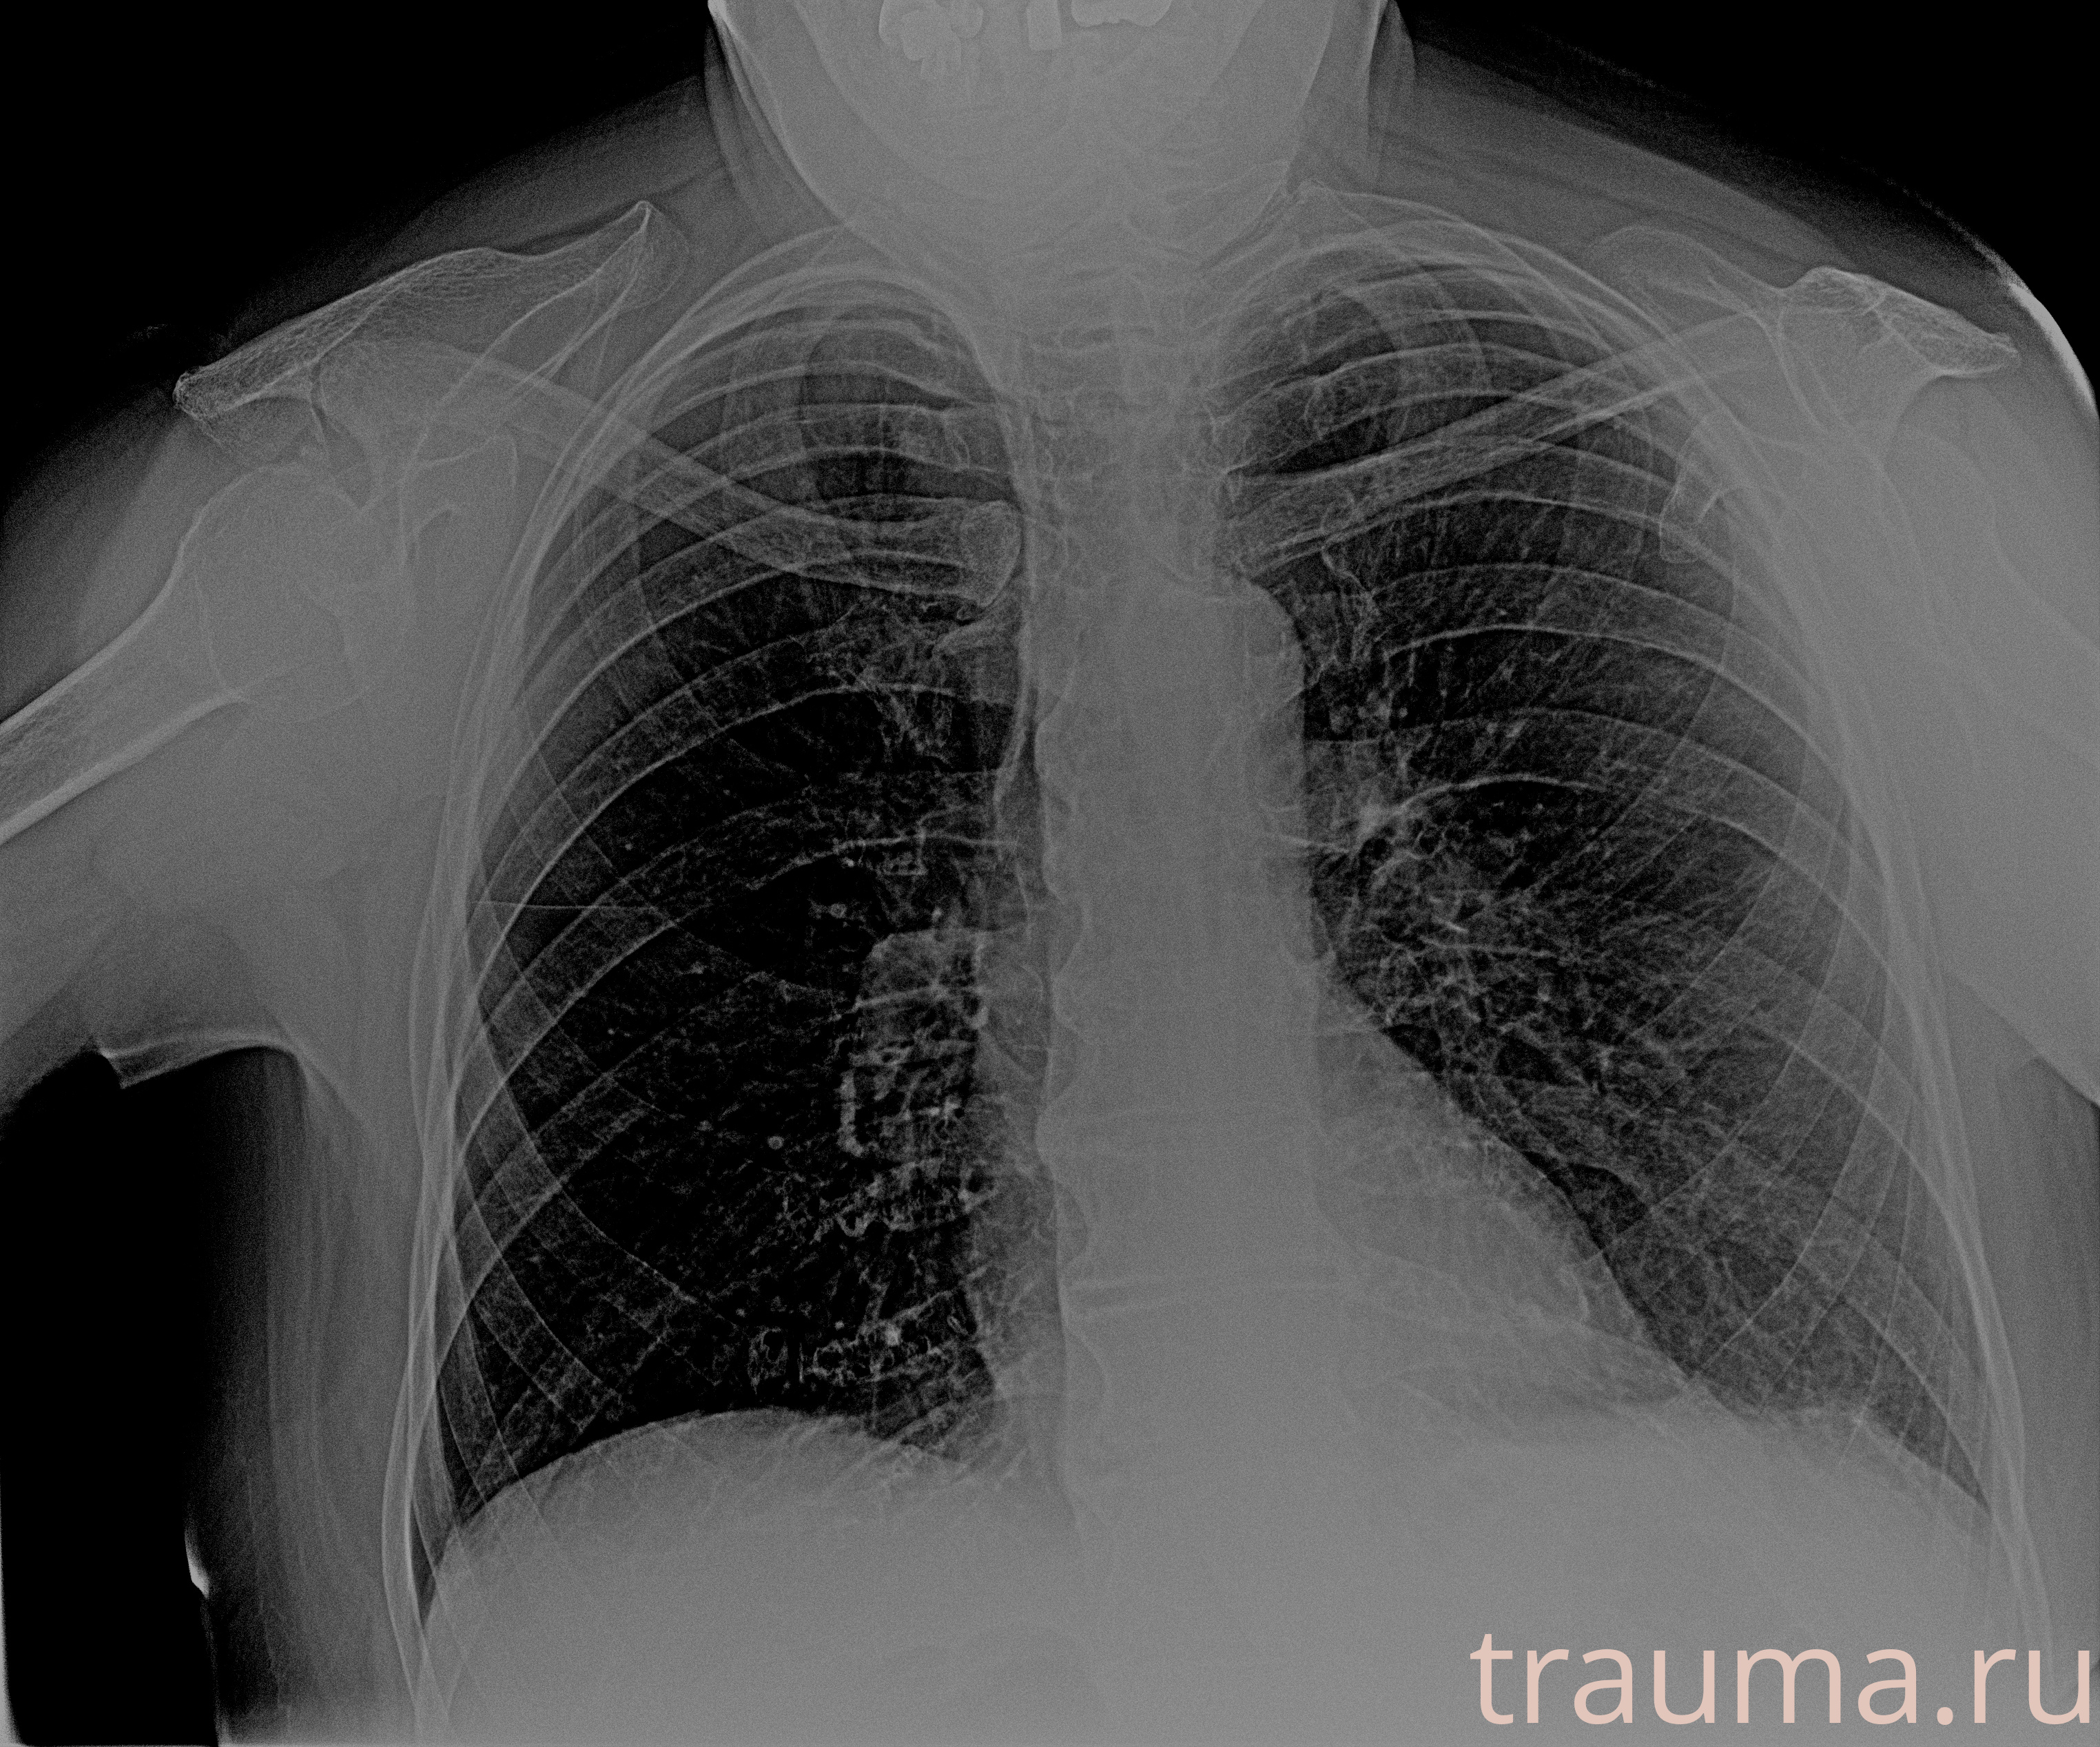

Рентген на дому: по вашему адресу приезжает врач-рентгенолог, травматолог-ортопед с мобильным рентгеновским аппаратом, проводит диагностику травмы или заболевания, делает необходимые рентгенограммы, дает рекомендации по дальнейшему лечению. Получить качественные снимки в домашних условиях возможно благодаря уникальной методике, разработанной МосРентген Центром для института  Склифосовского

при переломе шейки бедра и пневмонии от компании МосРентген Центр - партнера Института имени Склифосовского